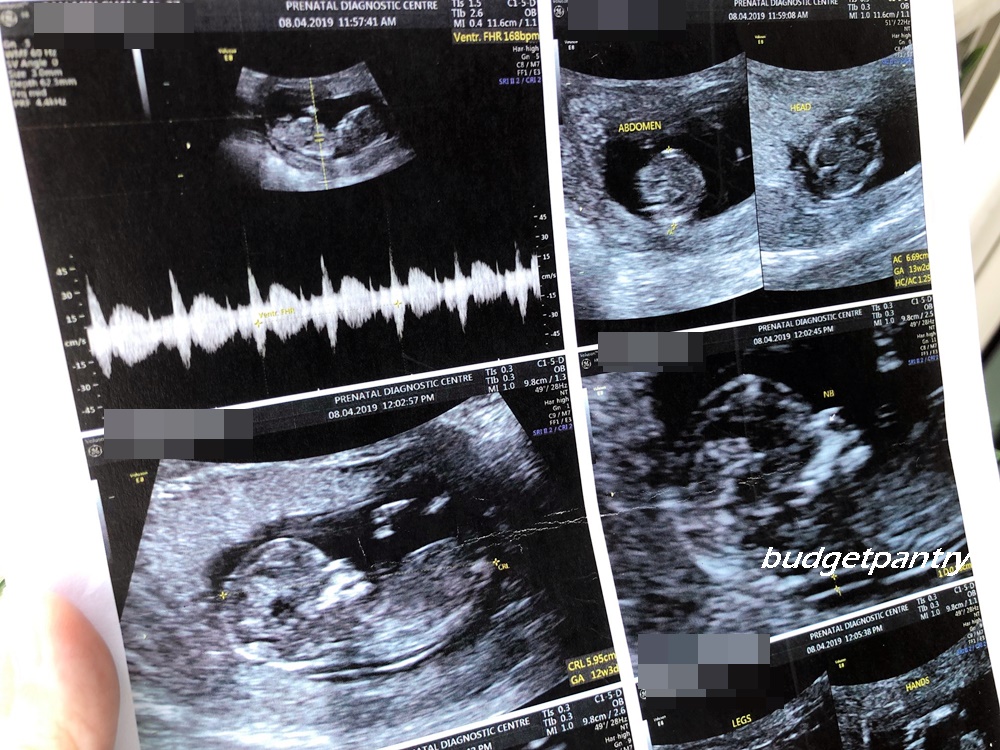

From www.budgetpantry.com

Pregnancy 2 The second trimester harmony test, NT scans and gender Boy Baby Nt Scan Report an nt scan is a common screening test that occurs during the first trimester of pregnancy. how to find baby gender in scan report. a nuchal translucency (nt) scan is an ultrasound scan to measure the amount of fluid at the back of your baby's. the nuchal translucency test (also called the nt scan) uses ultrasound. Boy Baby Nt Scan Report.